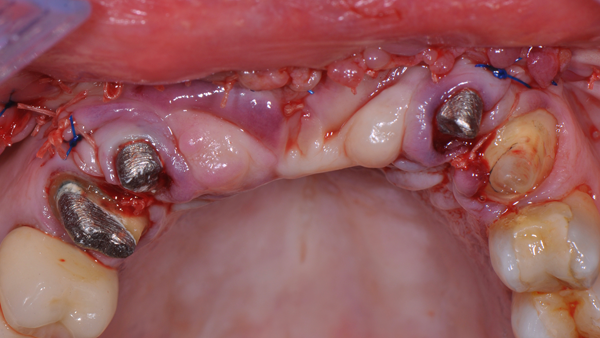

Foi utilizada uma membrana de politetrafl uoretileno denso (PTFE-d) reforçada com titânio (Cytoplast Ti250PS 20 mm x 25 mm, Osteogenics Biomedical) e osso heterógeno bovino (Lumina Porous, Critéria Biomateriais). O desenho do retalho invertido de base palatina (descrito anteriormente) foi escolhido para garantir fechamento após o procedimento de enxerto ósseo, apesar da dimensão aumentada da crista. Após o acesso ósseo, a membrana foi fixada com parafusos na região palatina (Figura 6) e o leito receptor foi preparado com penetrações múltiplas na cortical, usando uma pequena fresa (Figura 7).

O enxerto ósseo heterógeno foi acomodado no leito receptor e coberto com a membrana Cytoplast reforçada com titânio (Figura 8), que foi estabilizada com parafusos de fixação (Kit GBR, NeoBiotech), Figura 9.

Uma vez que a membrana foi completamente fixada, o retalho foi mobilizado para permitir o fechamento primário livre de tensão. O retalho foi suturado em duas camadas: primeiro, as suturas horizontais em colchoeiro e, depois, as suturas simples para fechar as bordas do retalho (Figura 10). As suturas simples foram removidas 14 dias após a cirurgia e as suturas em colchoeiro horizontais foram removidas três semanas mais tarde. A membrana foi então removida após 25 semanas de cicatrização usando um retalho crestal de espessura total (Figuras 11 a 14).